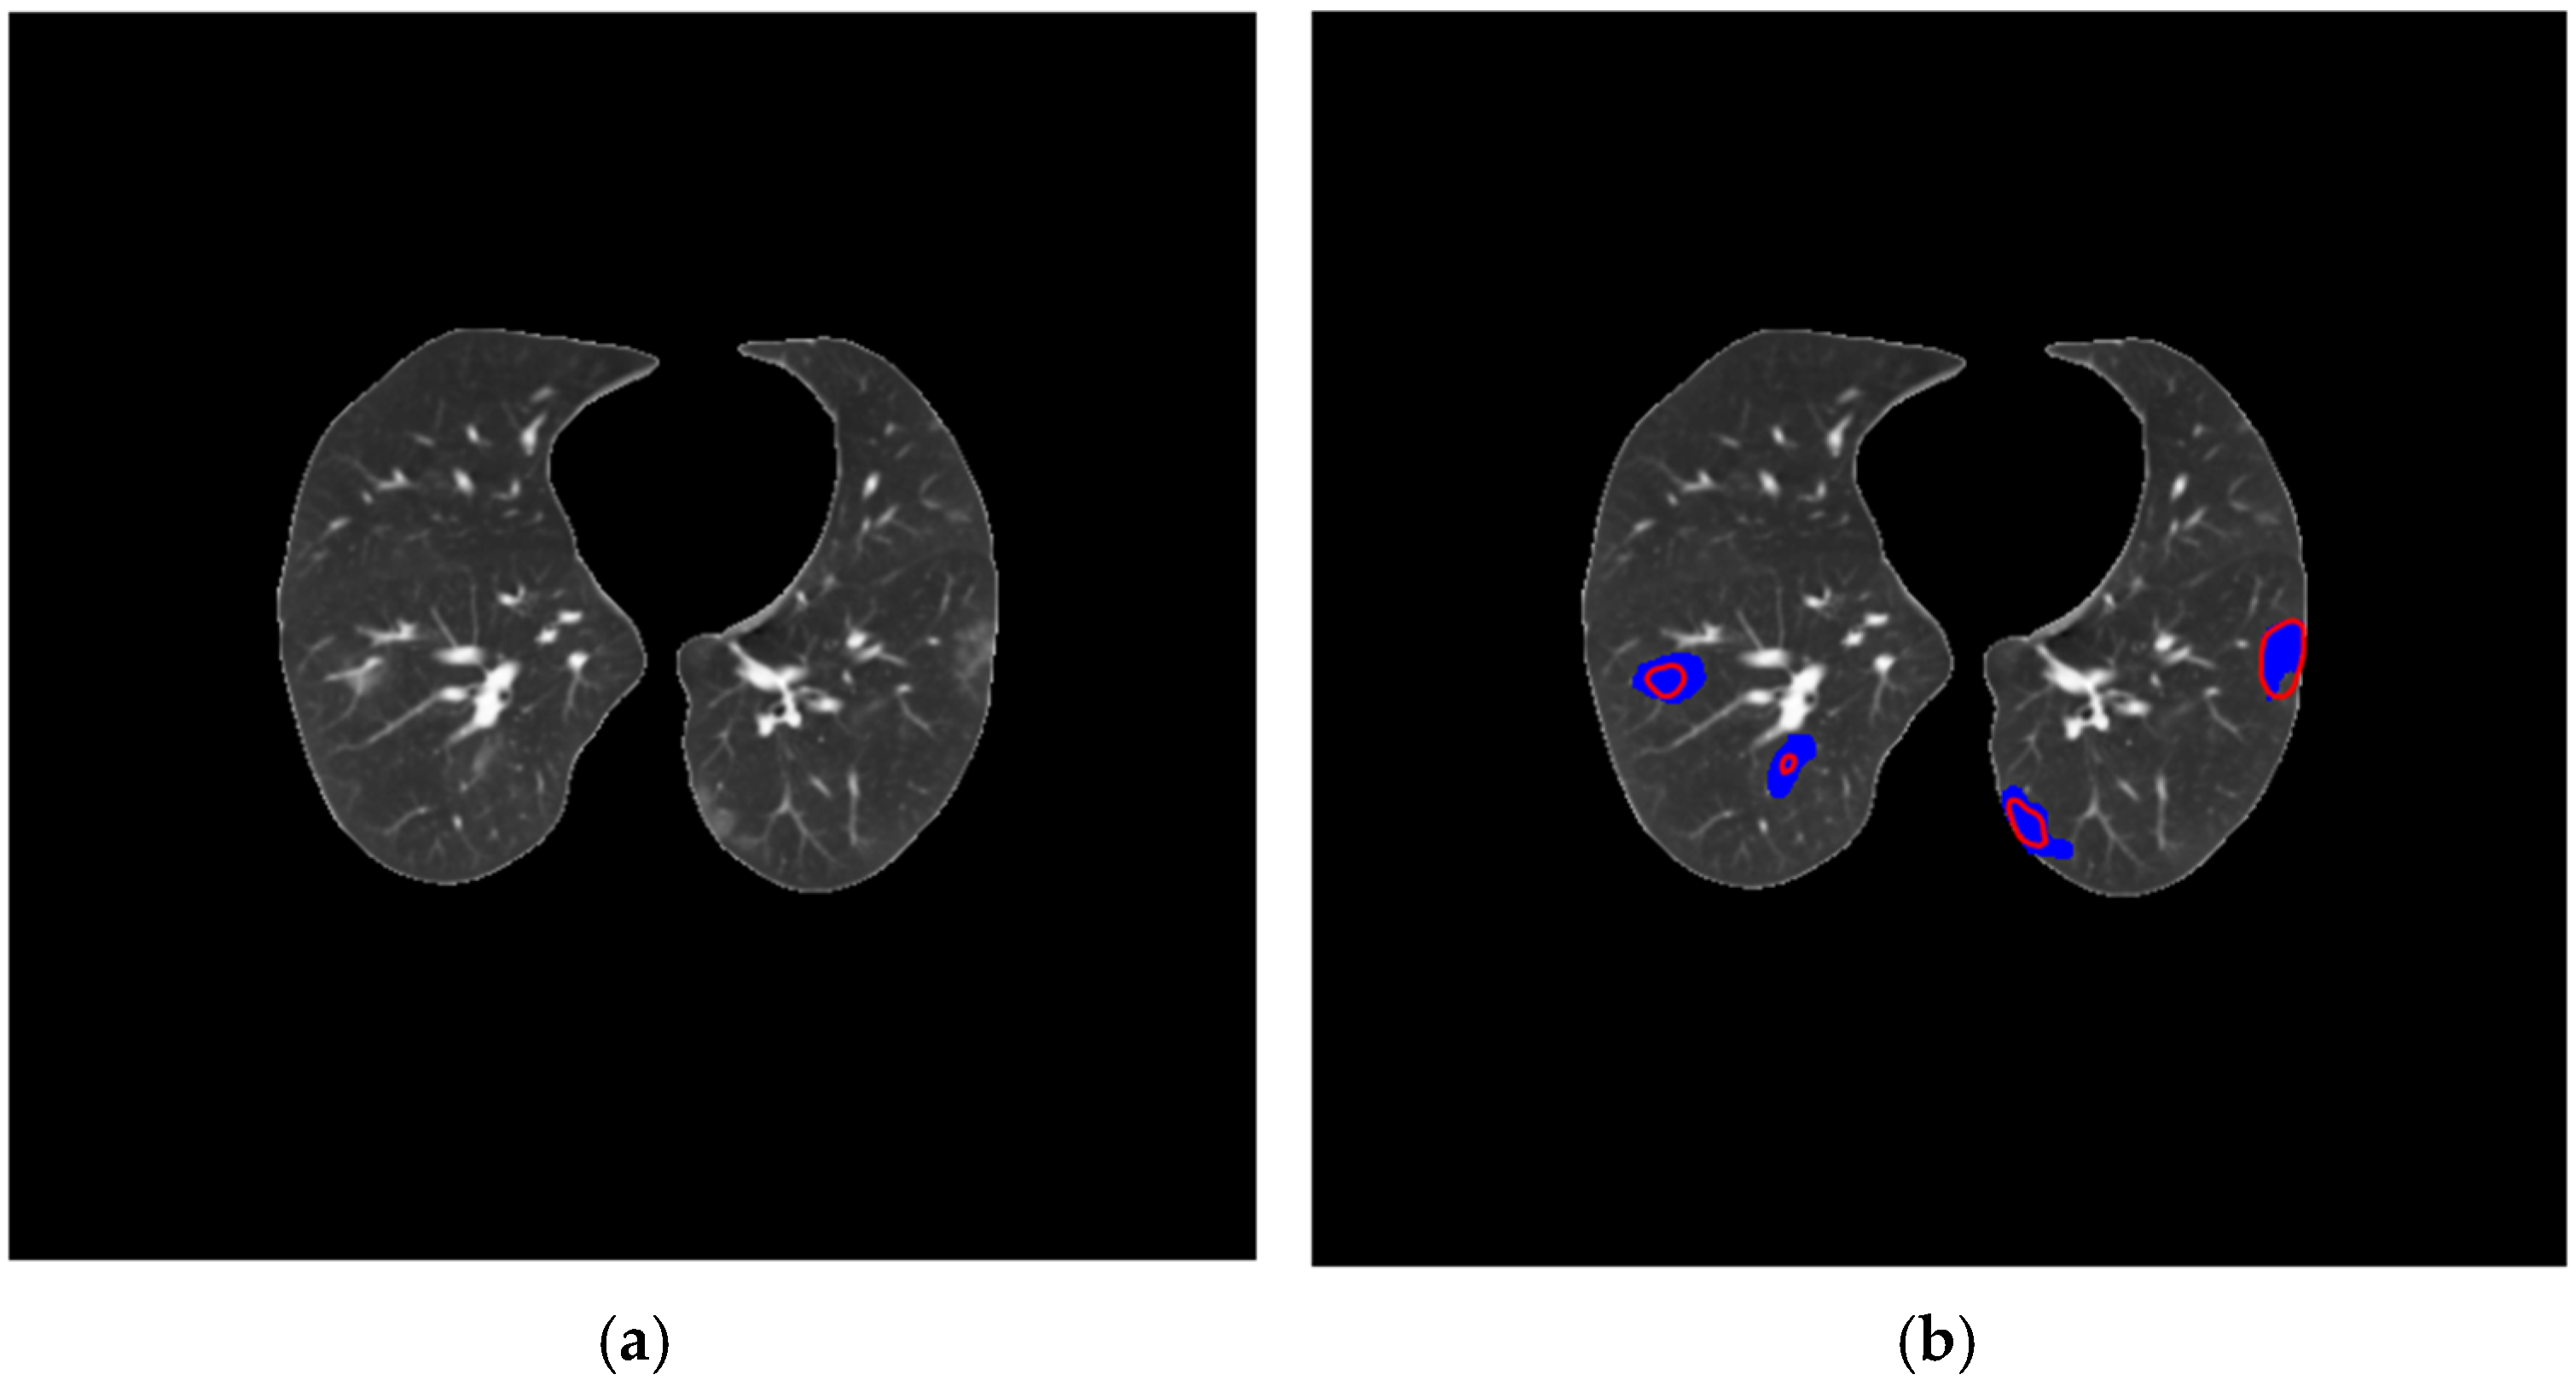

3.5. Lung and COVID-19 Segmentation Examples

3.2. COVID-19 Segmentation Results